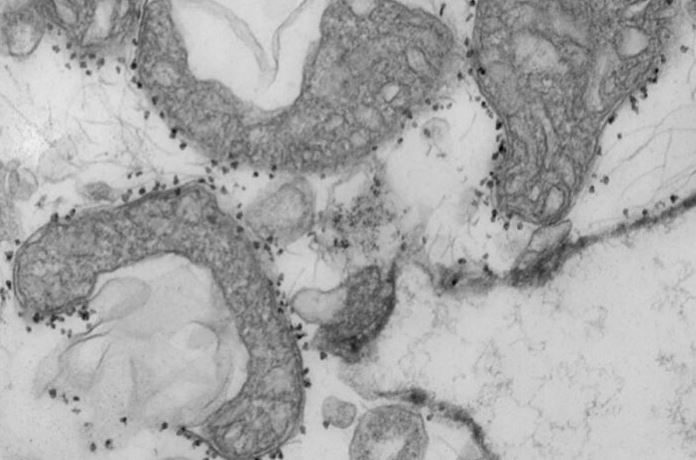

«Уровни митохондриальной ДНК являются мерой повреждения ткани. На фото - поврежденные митохондрии (темно-серые участки), высвобождающиеся из легких человека. Маленькие темные точки, окружающие митохондрии, представляют собой магнитные шарики, которые несут антитела, используемые для выделения и изучения нездоровых митохондрий, которые были высвобождены из умирающих тканей», - пишут авторы исследования.